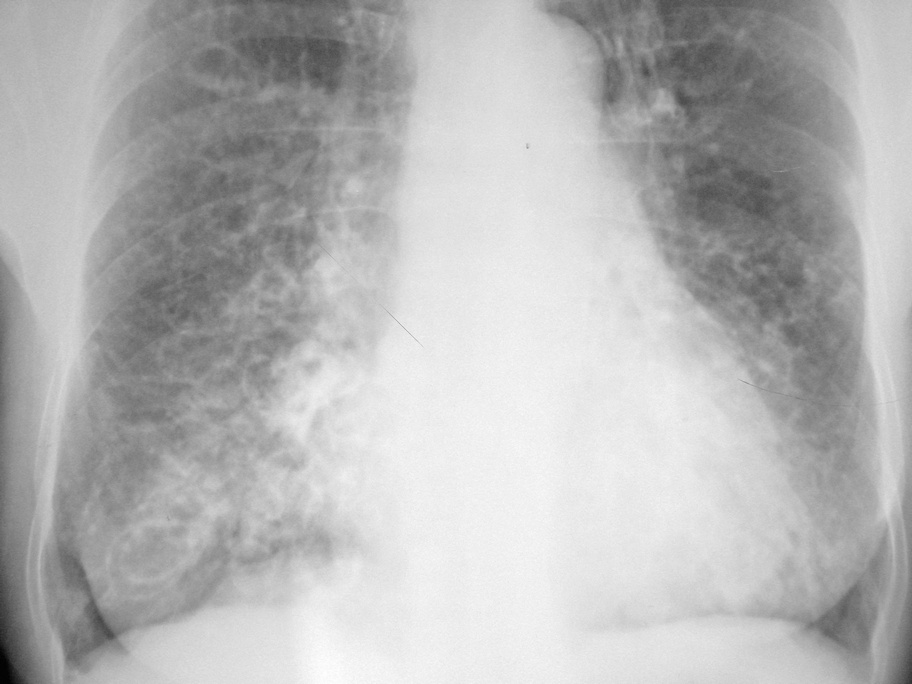

以下是引用拾荒者在2010-9-3 21:20:00的发言:[br]双肺纹理粗乱、模糊,双肺中下野沿纹理示卷发样改变,双侧胸廓饱满,膈肌低平,结合临床考虑:慢支并感染,肺气肿,支扩可能。